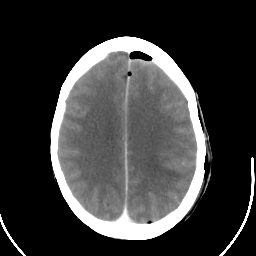

Metastatic bronchogenic carcinoma: Roentgen-ray CT (post-op) -- Slice #15

[Home][Help][Clinical] Slice 15